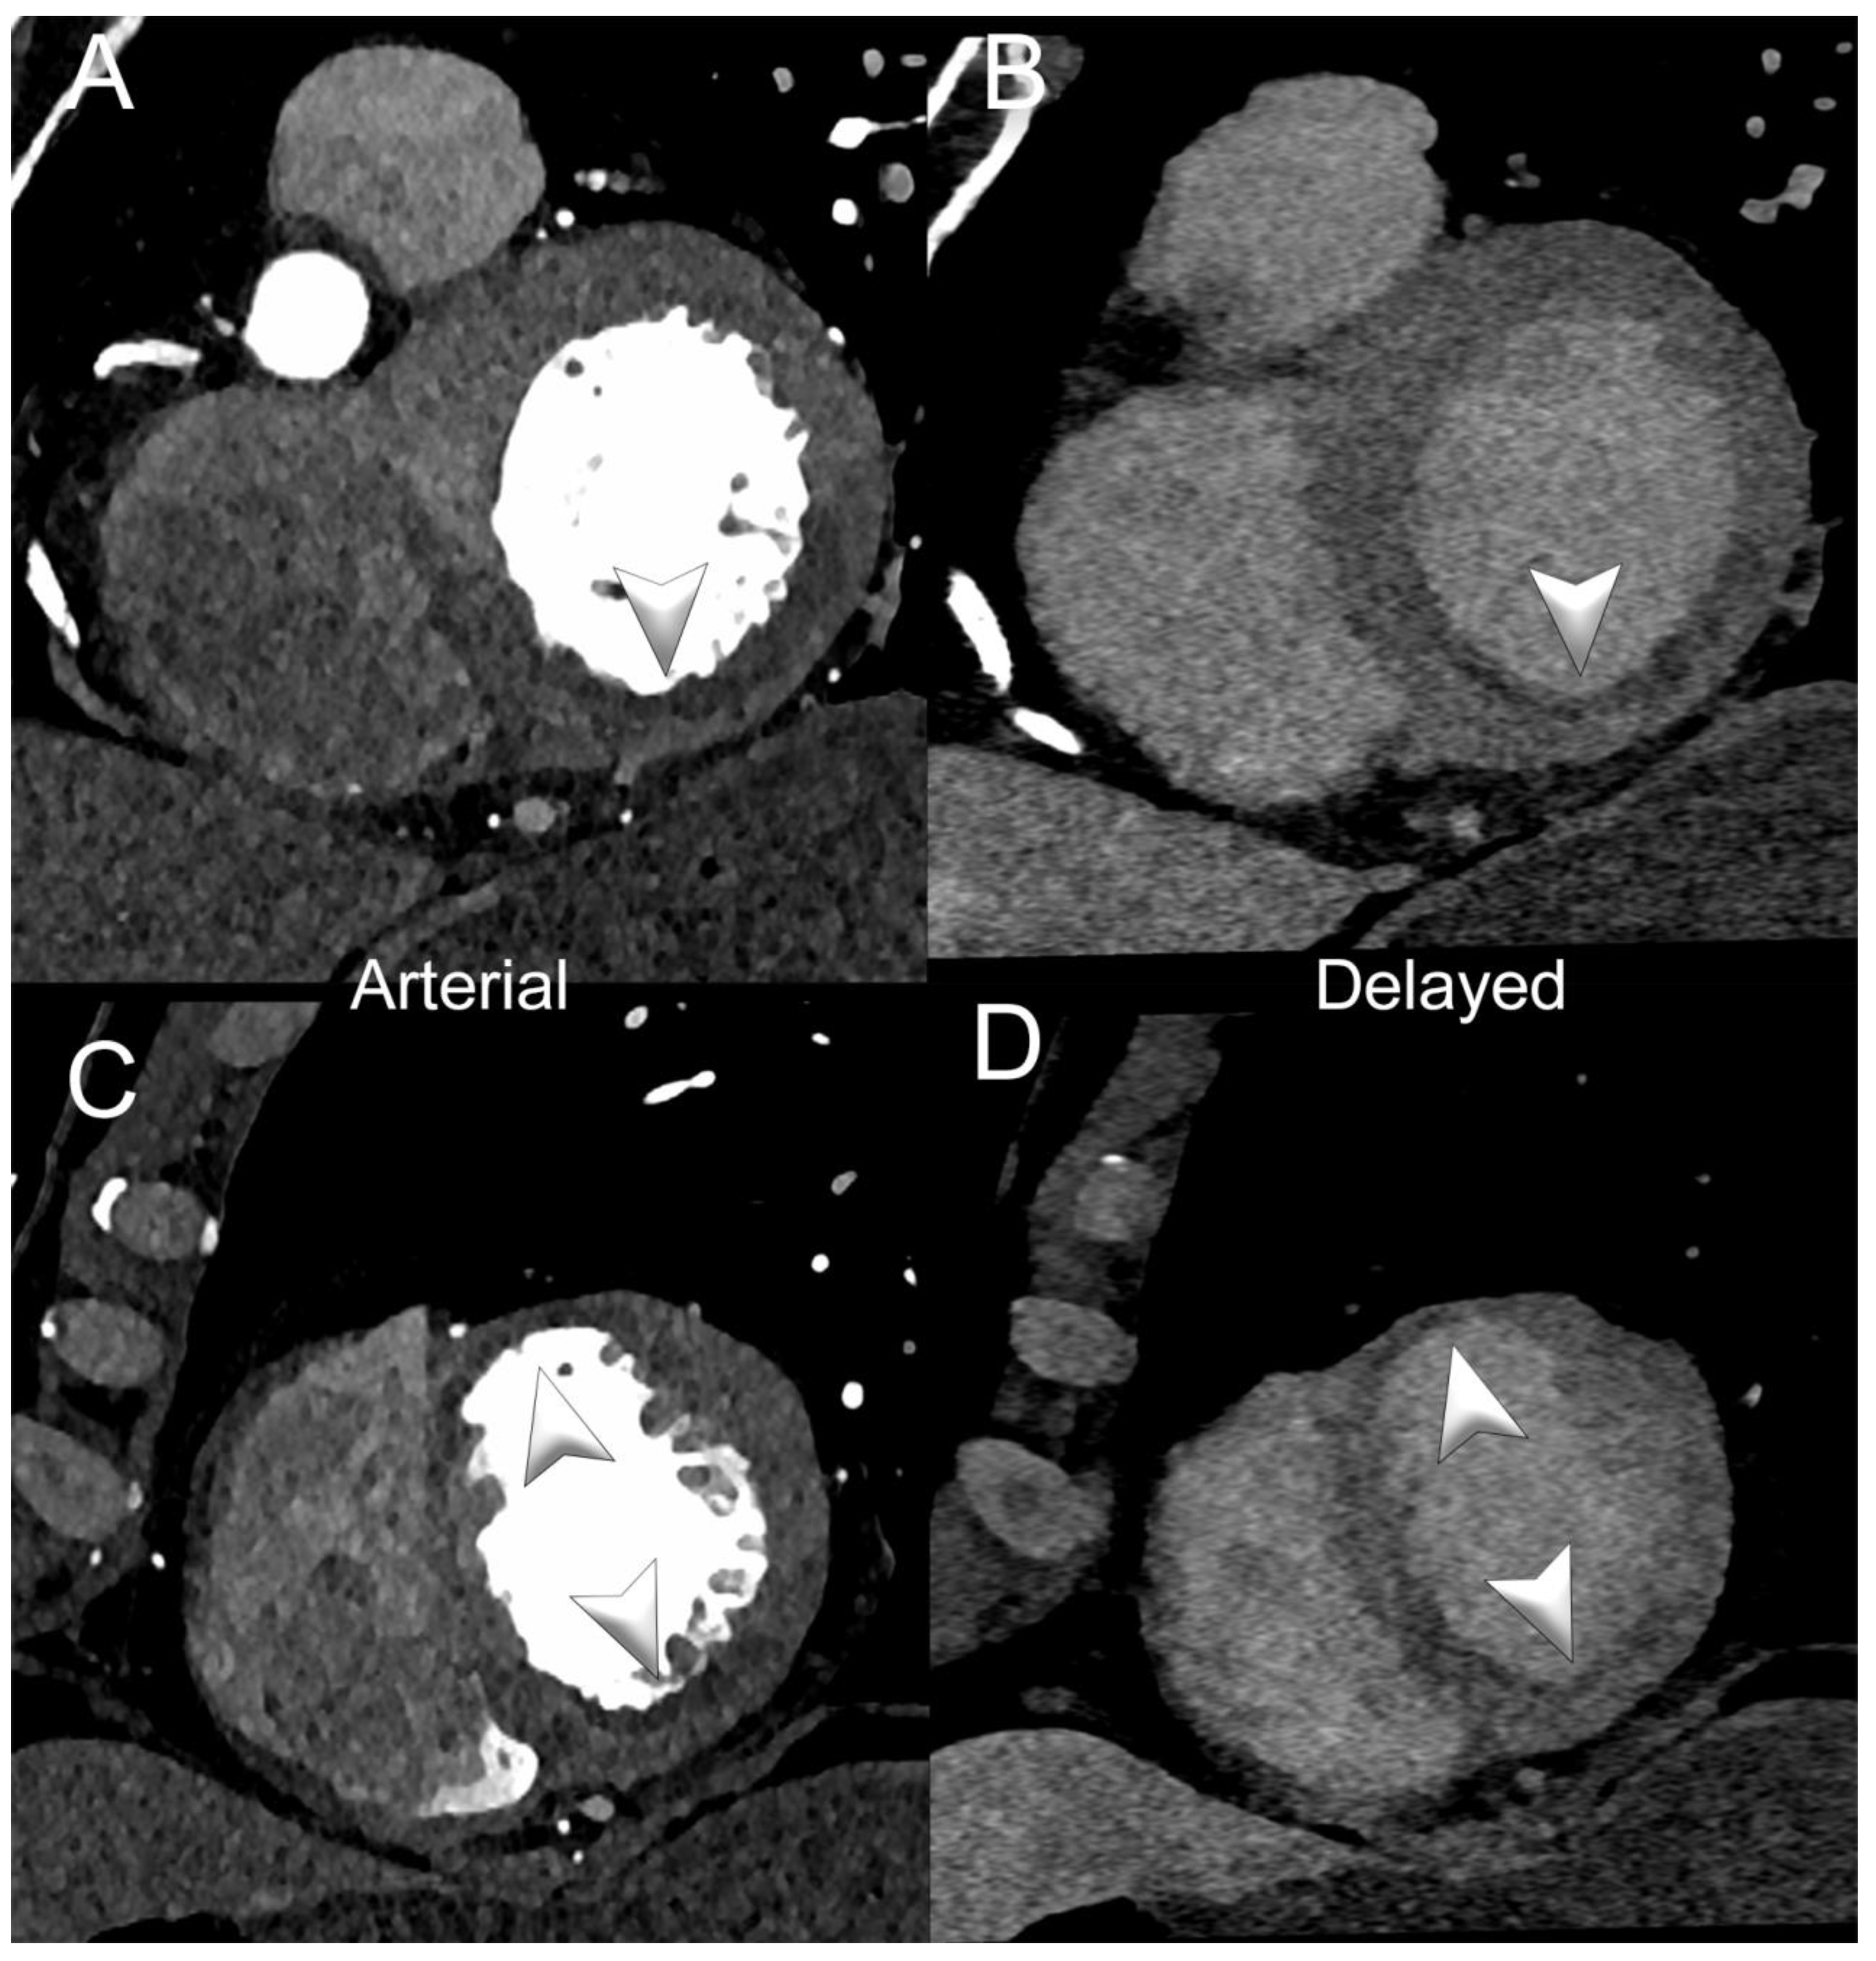

3.2. Myocardial Perfusion

3.3. Myocardial Tissue Characterization